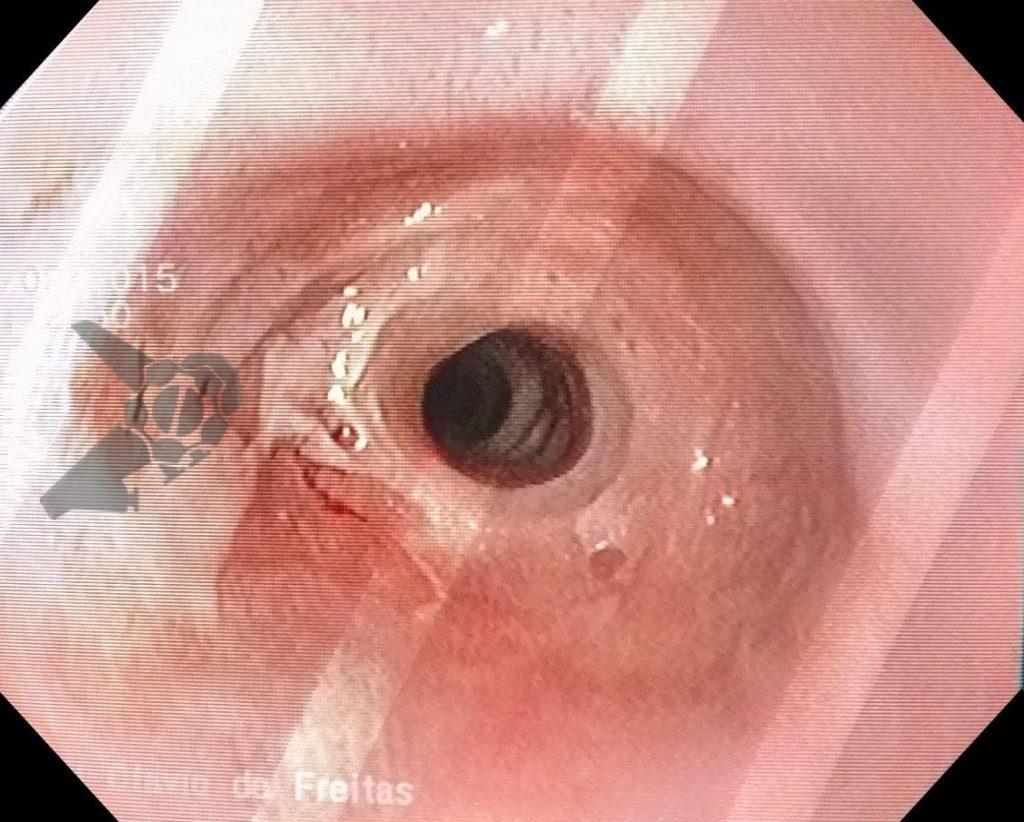

Sem entrar no mérito dos benefícios, eventos adversos após colonoscopia podem estar relacionados ao preparo colônico, sedação e ao procedimento em si, incluindo neste último dor abdominal, sangramento, perfuração e distensão abdominal. Todas estas complicações são bem descritas e conhecidas pelos colonoscopistas.

A queixa de dor abdominal após colonoscopia pode ser considerada uma manifestação comum, habitualmente associada a distensão gasosa e tração secundária ao exame, porém podem estar relacionadas a diversas outras causas. Pacientes com dor contínua, persistente ou em ascensão, associada ou não a sintomas como náuseas, vômitos, distensão abdominal relevante, hipotensão e instabilidade hemodinâmica devem despertar a atenção sobre possibilidade de perfuração, hemorragia ou lesão à órgãos intra-abdominais. Dentre as lesões de órgãos sólidos, a publicação destaca: